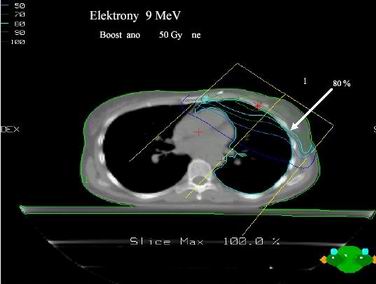

- dozáření lůžka tumoru 10 – 16 Gy = zlepšení lokální kontroly onemocnění Přímé elektronové pole nebo intersticiální BRT

Dvě tangenciální hrudní pole

většinou s klíny

A jedno přímé pole nadklíček + boost axilla Pa pole (8 Gy)

Společné izocentrum pro všechna pole